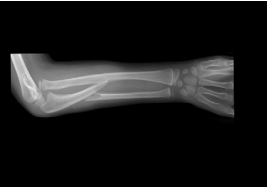

53 10 歲患者主訴於玩吊單槓跌倒落地,右肘、右前臂腫脹疼痛異常就診,X 光顯示如圖,下列敘述何 者錯誤? (A)診斷為孟氏骨折(Monteggia’s Fracture),尺骨上 1/3 骨折合併橈骨頭脫位 (B)分類為伸直型 (C)其復位手法為先整復尺骨骨折,後整復橈骨頭脫位 (D)骨折脫位復位後,應先將肘關節固定於屈肘位